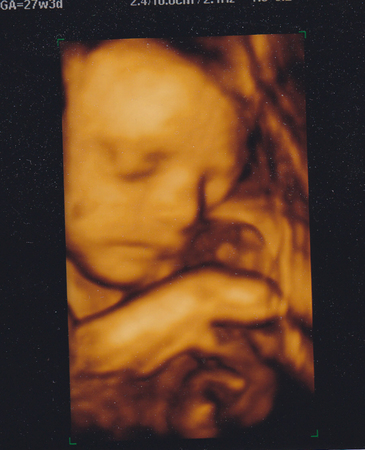

Вот наш первый портрет

А тут наш пирожок

(я сначала подумала что это яйки, испугалась, но УЗИстка сказала, что я неенормальная! Какие же это яйки !? это ПИРОЖОК!!!!!)

эт она не грустная, эт она уже спать укладывалась, перед этим улыбалась даже, но фотки плохо получились: пуповина перед лицом болталась

Это дынька!)))

Такая грустнулька на фото)